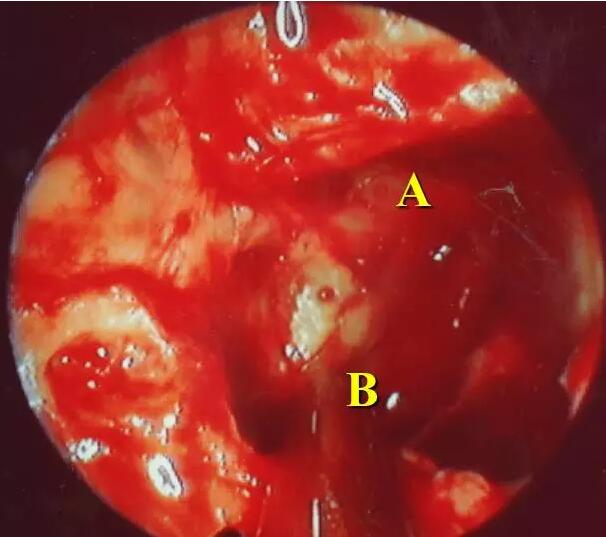

蝶窦内管型视神经管(A.视神经管 B. 颈内动脉)

视神经管隆起和颈内动脉管隆起交叉(A. 视神经管 B. 颈内动脉)